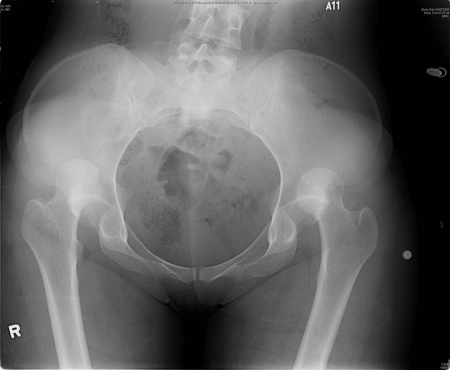

X-ray showing bilateral hip posterior dislocation

Fan KY, et al. BMJ Case Rep. 2015 Mar 25:2015:bcr2014204031; used with permission